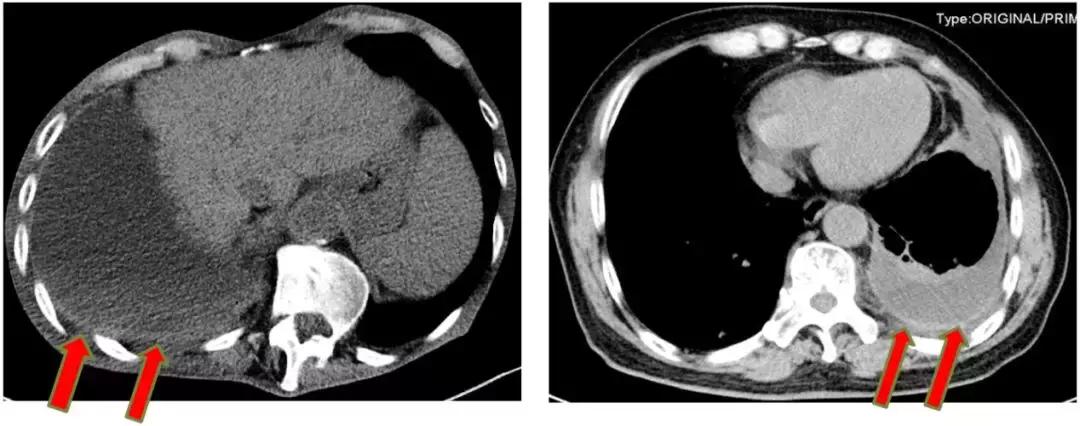

仔细阅读CT,识别胸膜增厚点是成功的第一步

我们可以看到CT图像上,选择胸膜较厚的地方来进行穿刺,阳性率较高,反之阳性率较低(箭头为增厚部位)。

适合盲穿活检的胸腔积液 >>

胸膜弥漫性增厚,在相对比较弥漫的地方确定安全的进针点进行穿刺。

如下图,选择增厚、病变比较明显的地方进行穿刺,阳性率较高。